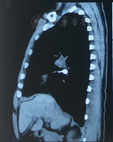

男性患者,55岁,因上颌后牙拔除后3个月,要求种植修复于2017年3月济南军区总医院口腔科就诊。口内检查情况为26、27缺失,拟在26、27位点植入两枚4.8 mm×10.0 mm种植体。手术开始后,患者咽反射明显,不停要求吸出口内分泌物,吸引器吸引时又出现恶心咳嗽,立即停止手术,与患者沟通后认为患者尚可耐受手术,休息后患者状态良好,采取改变椅位角度、在咽部放置纱布等措施进行保护,旋入27种植体愈合基台时纱布影响操作,遂取出纱布在旋紧27种植体愈合基台完成后,患者突然剧烈咳嗽闭合口唇,螺丝刀掉落口内并被吞入。放平患者后进行椅旁X线照射,示螺丝刀位于主支气管内,患者咳嗽但无呼吸不畅。胸部CT可见螺丝刀位于右侧主支气管内(图1,图2),六方刀口朝上,利于纤维支气管镜取出。呼吸内科医师在充分麻醉下,使用电子纤维支气管镜异物夹持器械(软管)取出异物(图3)。患者无咳嗽,常规口服三日抗生素(阿莫西林、甲硝唑)预防肺部感染。

(3)异物位置、症状:误吸的异物大部分位于右主支气管,其次是左主支气管、右肺,几乎没有异物掉落至左肺的病例报道[3]。发生误吸的患者可能出现咳嗽,仅有1例报道出现疼痛,1例恶心,但大部分报道病例症状不明显。仅凭症状很难判断异物位置,需借助影像学手段明确诊断[3]。